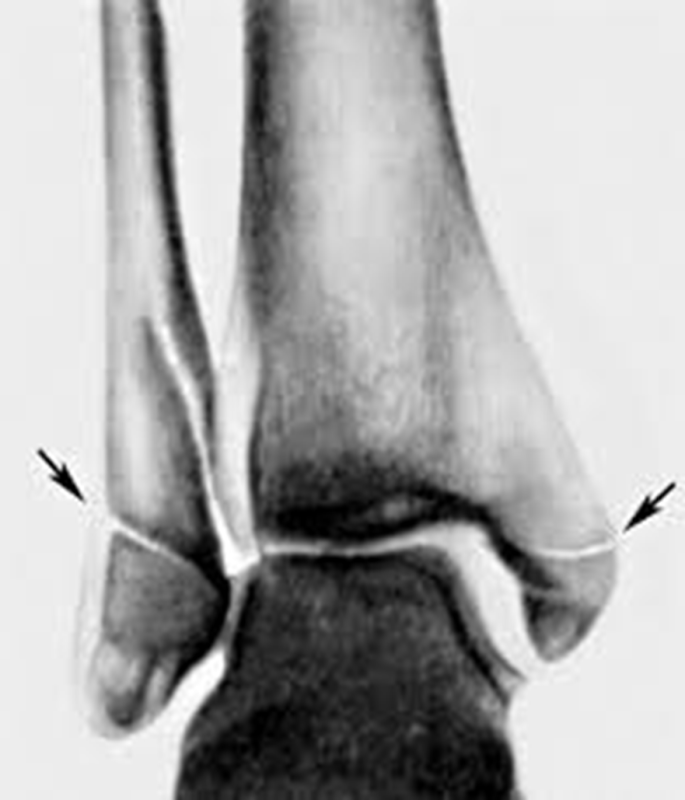

Апикальный перелом это